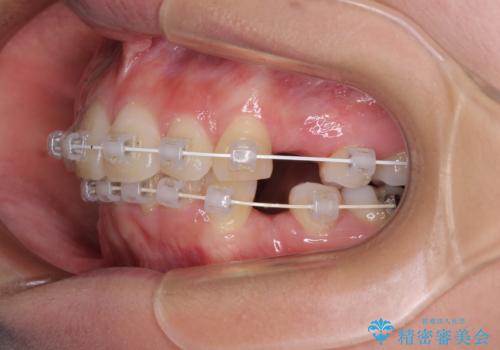

デコボコで飛び出した前歯 ワイヤー装置による抜歯矯正

口元を積極的に引っ込めるために、上下左右の小臼歯計4本を抜歯することとしました。

咬み合わせが深く、咬合力強いため、補助装置を使用しながら積極的に口元を下げることとしました。

矯正治療前の咬み合わせで、前歯がすり減ってしまい、歯列が整ったときに先端がガタガタになってしまったため、矯正治療後に形態修正を行いました。